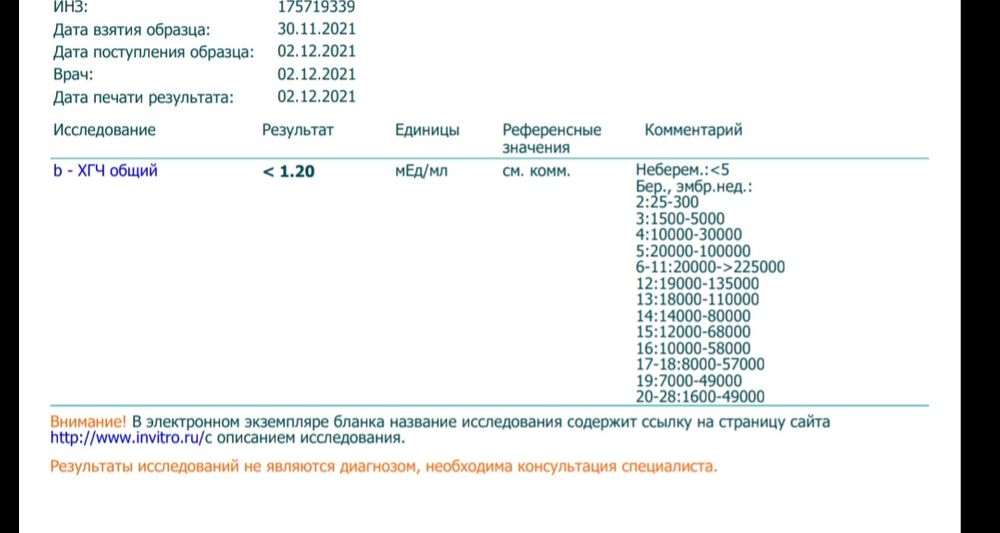

Привет писла ранее что было подозрение на ВБ, по вашим советам все таки сдала ХГЧ, результат прикрепила. Как я поняла что по результатам беременности нет. Возникает масса вопросов, на которые уже 3 врача не дают мне ответа. Возможно тут есть девочки которые сталкивались с подобной ситуацией. Больше всего мне интересно: может ли при не развитой ВБ быть такой показатель ХГЧ?

При внематочной беременности хгч больше. Для того,чтобы на узи что-то увидели-хгч должно быть больше 1000. 1.2 это полностью отрицательный результат

Буду мамой , но у меня 1.2. Но насколько я поняла врачей и девушку которая узи делала что если ХГЧ <5 то беременности вообще нет

При любой Бер,буть то внематочн,замершая ХГЧ растет как и при нормальной,только чуть медленнее. У вас ХГЧ не беременный,это 💯.